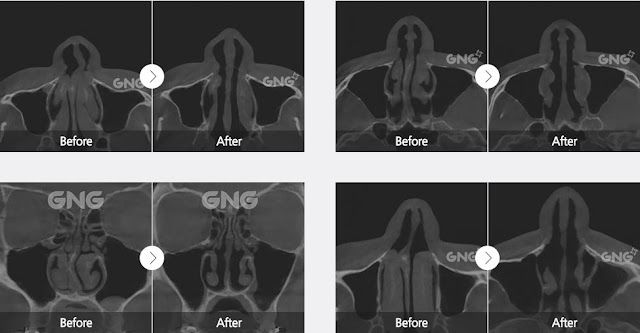

There are 3 types of functional surgery to fix deviated nose and inner structure.

1. Septoplasty: The nasal septum is opened to expose the septum cartilage and bones, then the deviated part is straightened, fixed in place, and the incision is sutured.

2. Turbinoplasty: After the nasal mucosa is incised, turbinate bones and the nasal mucosa are removed as much as necessary.

3. Nasal Valve Reconstruction: Autologous or donated cartilage is used to widen the narrow nasal valve.